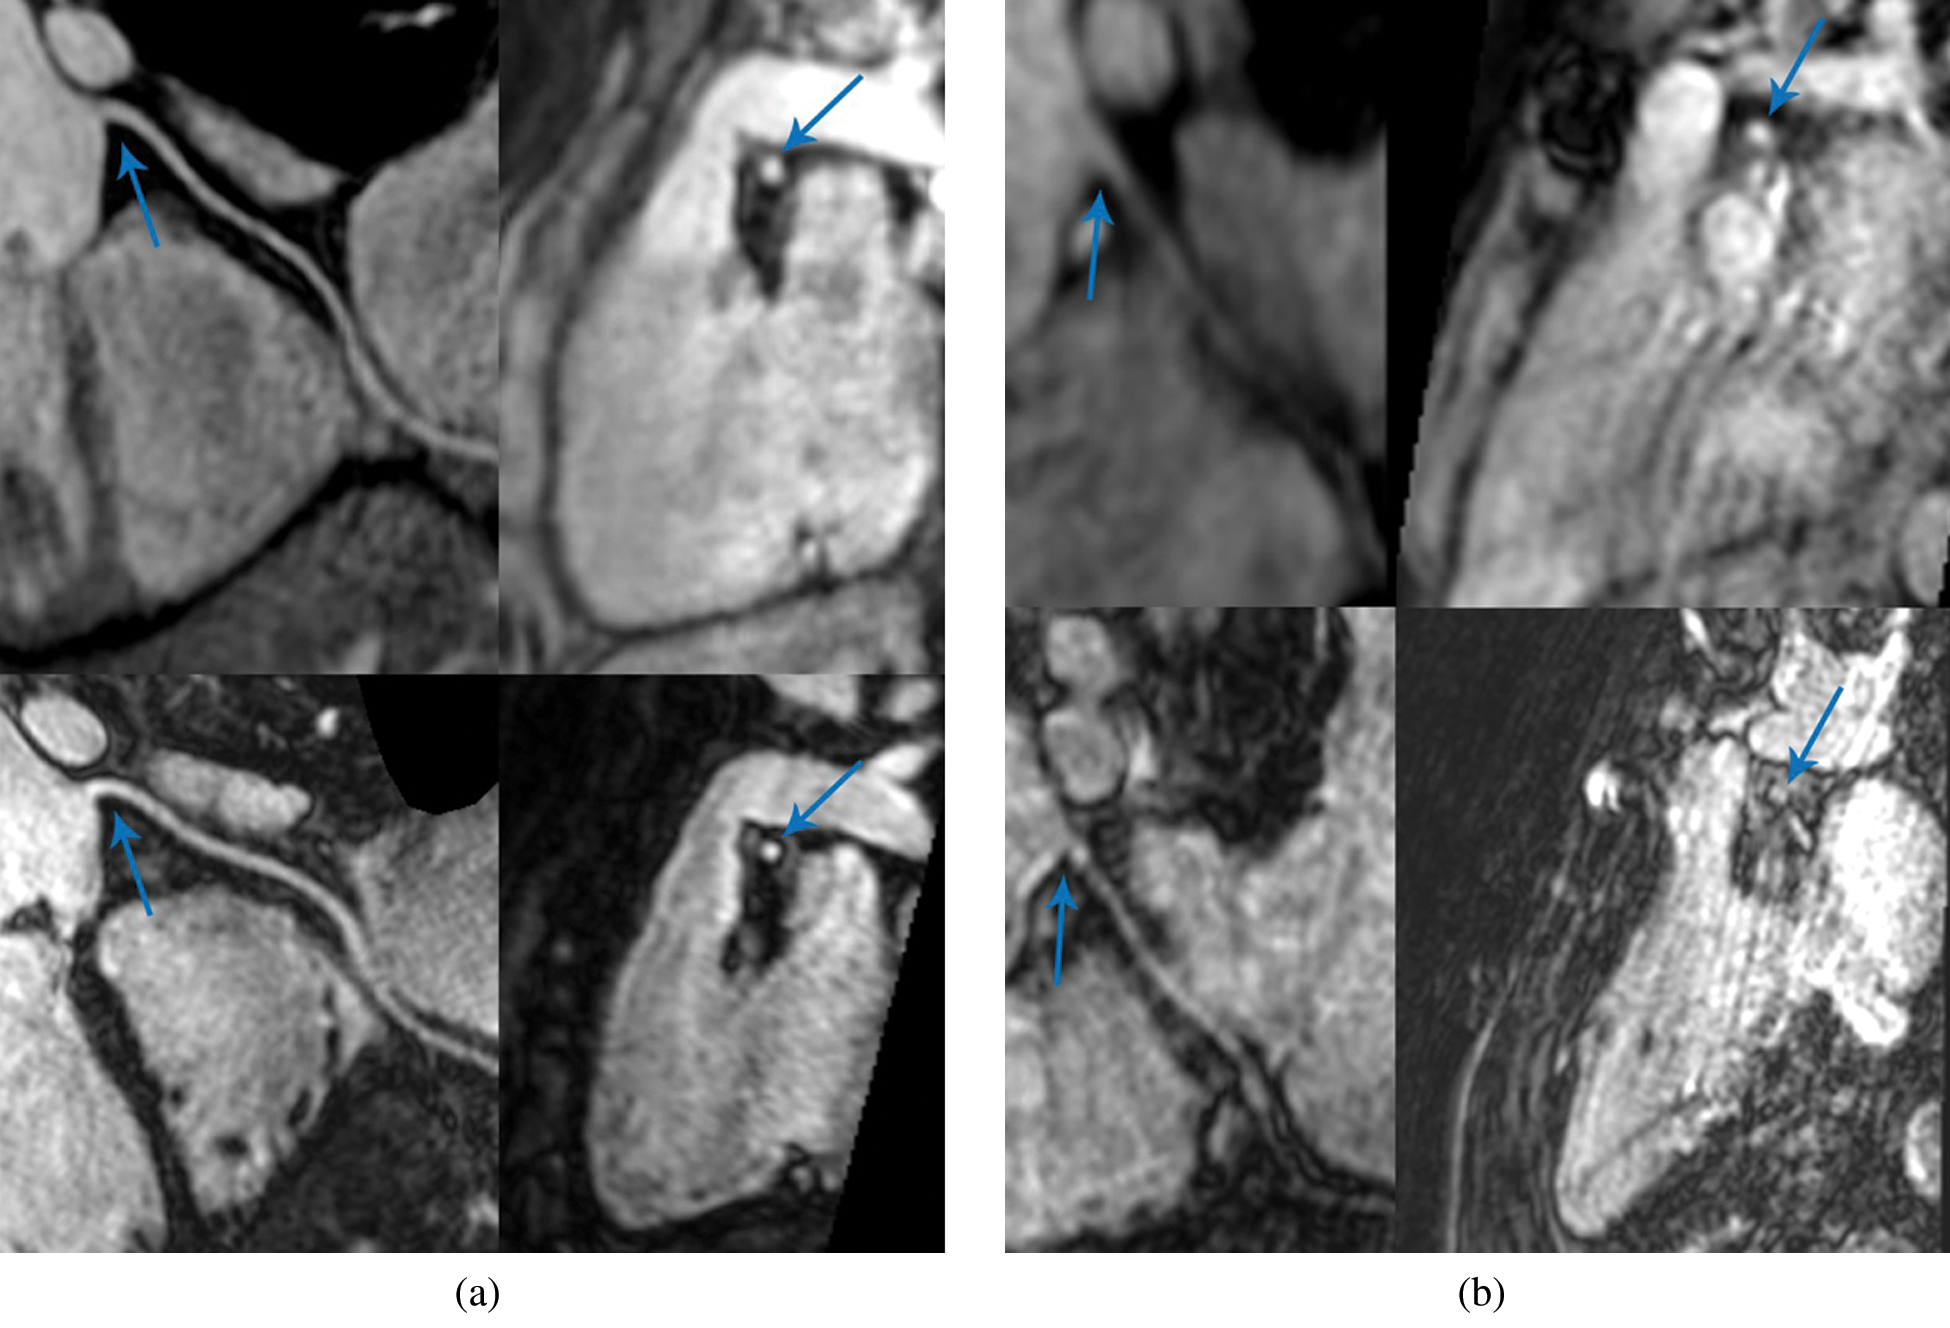

There was no significant difference in identifiable length measured on multi-planar reconstructions of SSFP and Gd-FLASH in the patient group, p > 0.2 (Tab. 2). The range of image quality of the coronary artery origin with SSFP and Gd-FLASH are illustrated in Fig. 2.

Figure 2: Coronary magnetic resonance angiography (CMRA). Multi-planar reconstruction (MPR) of the right coronary artery (RCA). (a) Shows a fourteen-year-old female patient with very good image quality. (b) Shows an eleven-year-old male patient with suboptimal image quality. In both images; Upper row: RCA reconstruction of steady-state free precession to the left and cross-section of the RCA ostium to the right (arrow). Lower row: RCA reconstruction of Gadolinium-enhanced fast low-angle shot to the left and cross-section of the RCA ostium to the right (arrow)